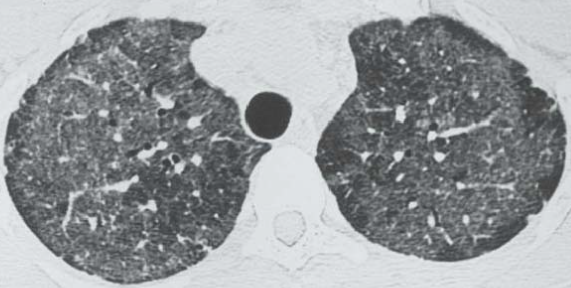

CT

- Patchs de VD bilatéral

- Crazy paving

- Central, péri-hilaire

- Prédominance dans les plages supérieures et péri-hilaire

patchs de VD bilatéraux, lobes sups